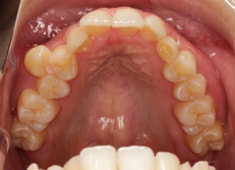

症例紹介

左上3番埋伏歯

治療法:フルパッシブブラケット:T21

治療開始から24ヶ月後